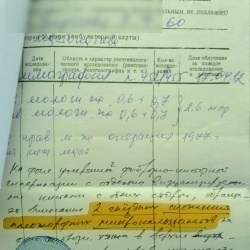

Уважаемые коллеги. Представляю вам клинический случай, вот думаю - как его лучше оформить. Наверное, выложу хронологически.

Пациентка 1951 г.р. Маммография 2011 г. - заключение: фиброзная...